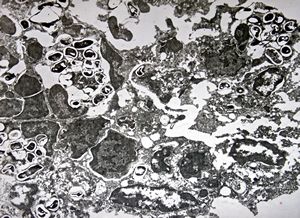

M,50y. | Pneumocystis carinii